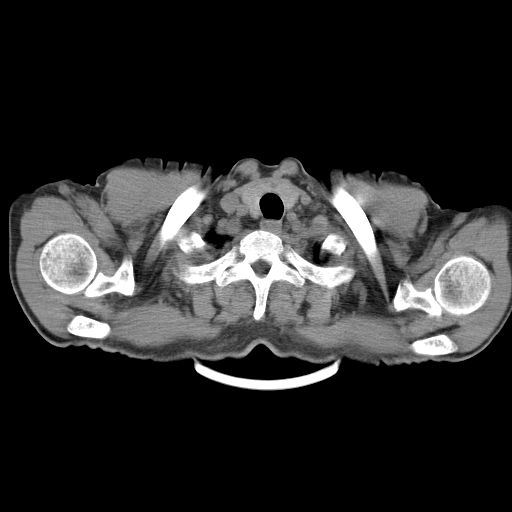

以下是引用心路寻觅在2010-3-1 10:23:00的发言:[br]1、考虑左肺上叶周围型肺癌[br]2、右上肺陈旧性病灶。[br][br][本贴已被 心路寻觅 于 2010-3-1 10:40:18 修改过]

以下是引用shuiyuan在2010-3-1 10:45:00的发言:[br]考虑左肺上叶中心型肺癌伴阻塞型炎症,邻近胸膜受侵。